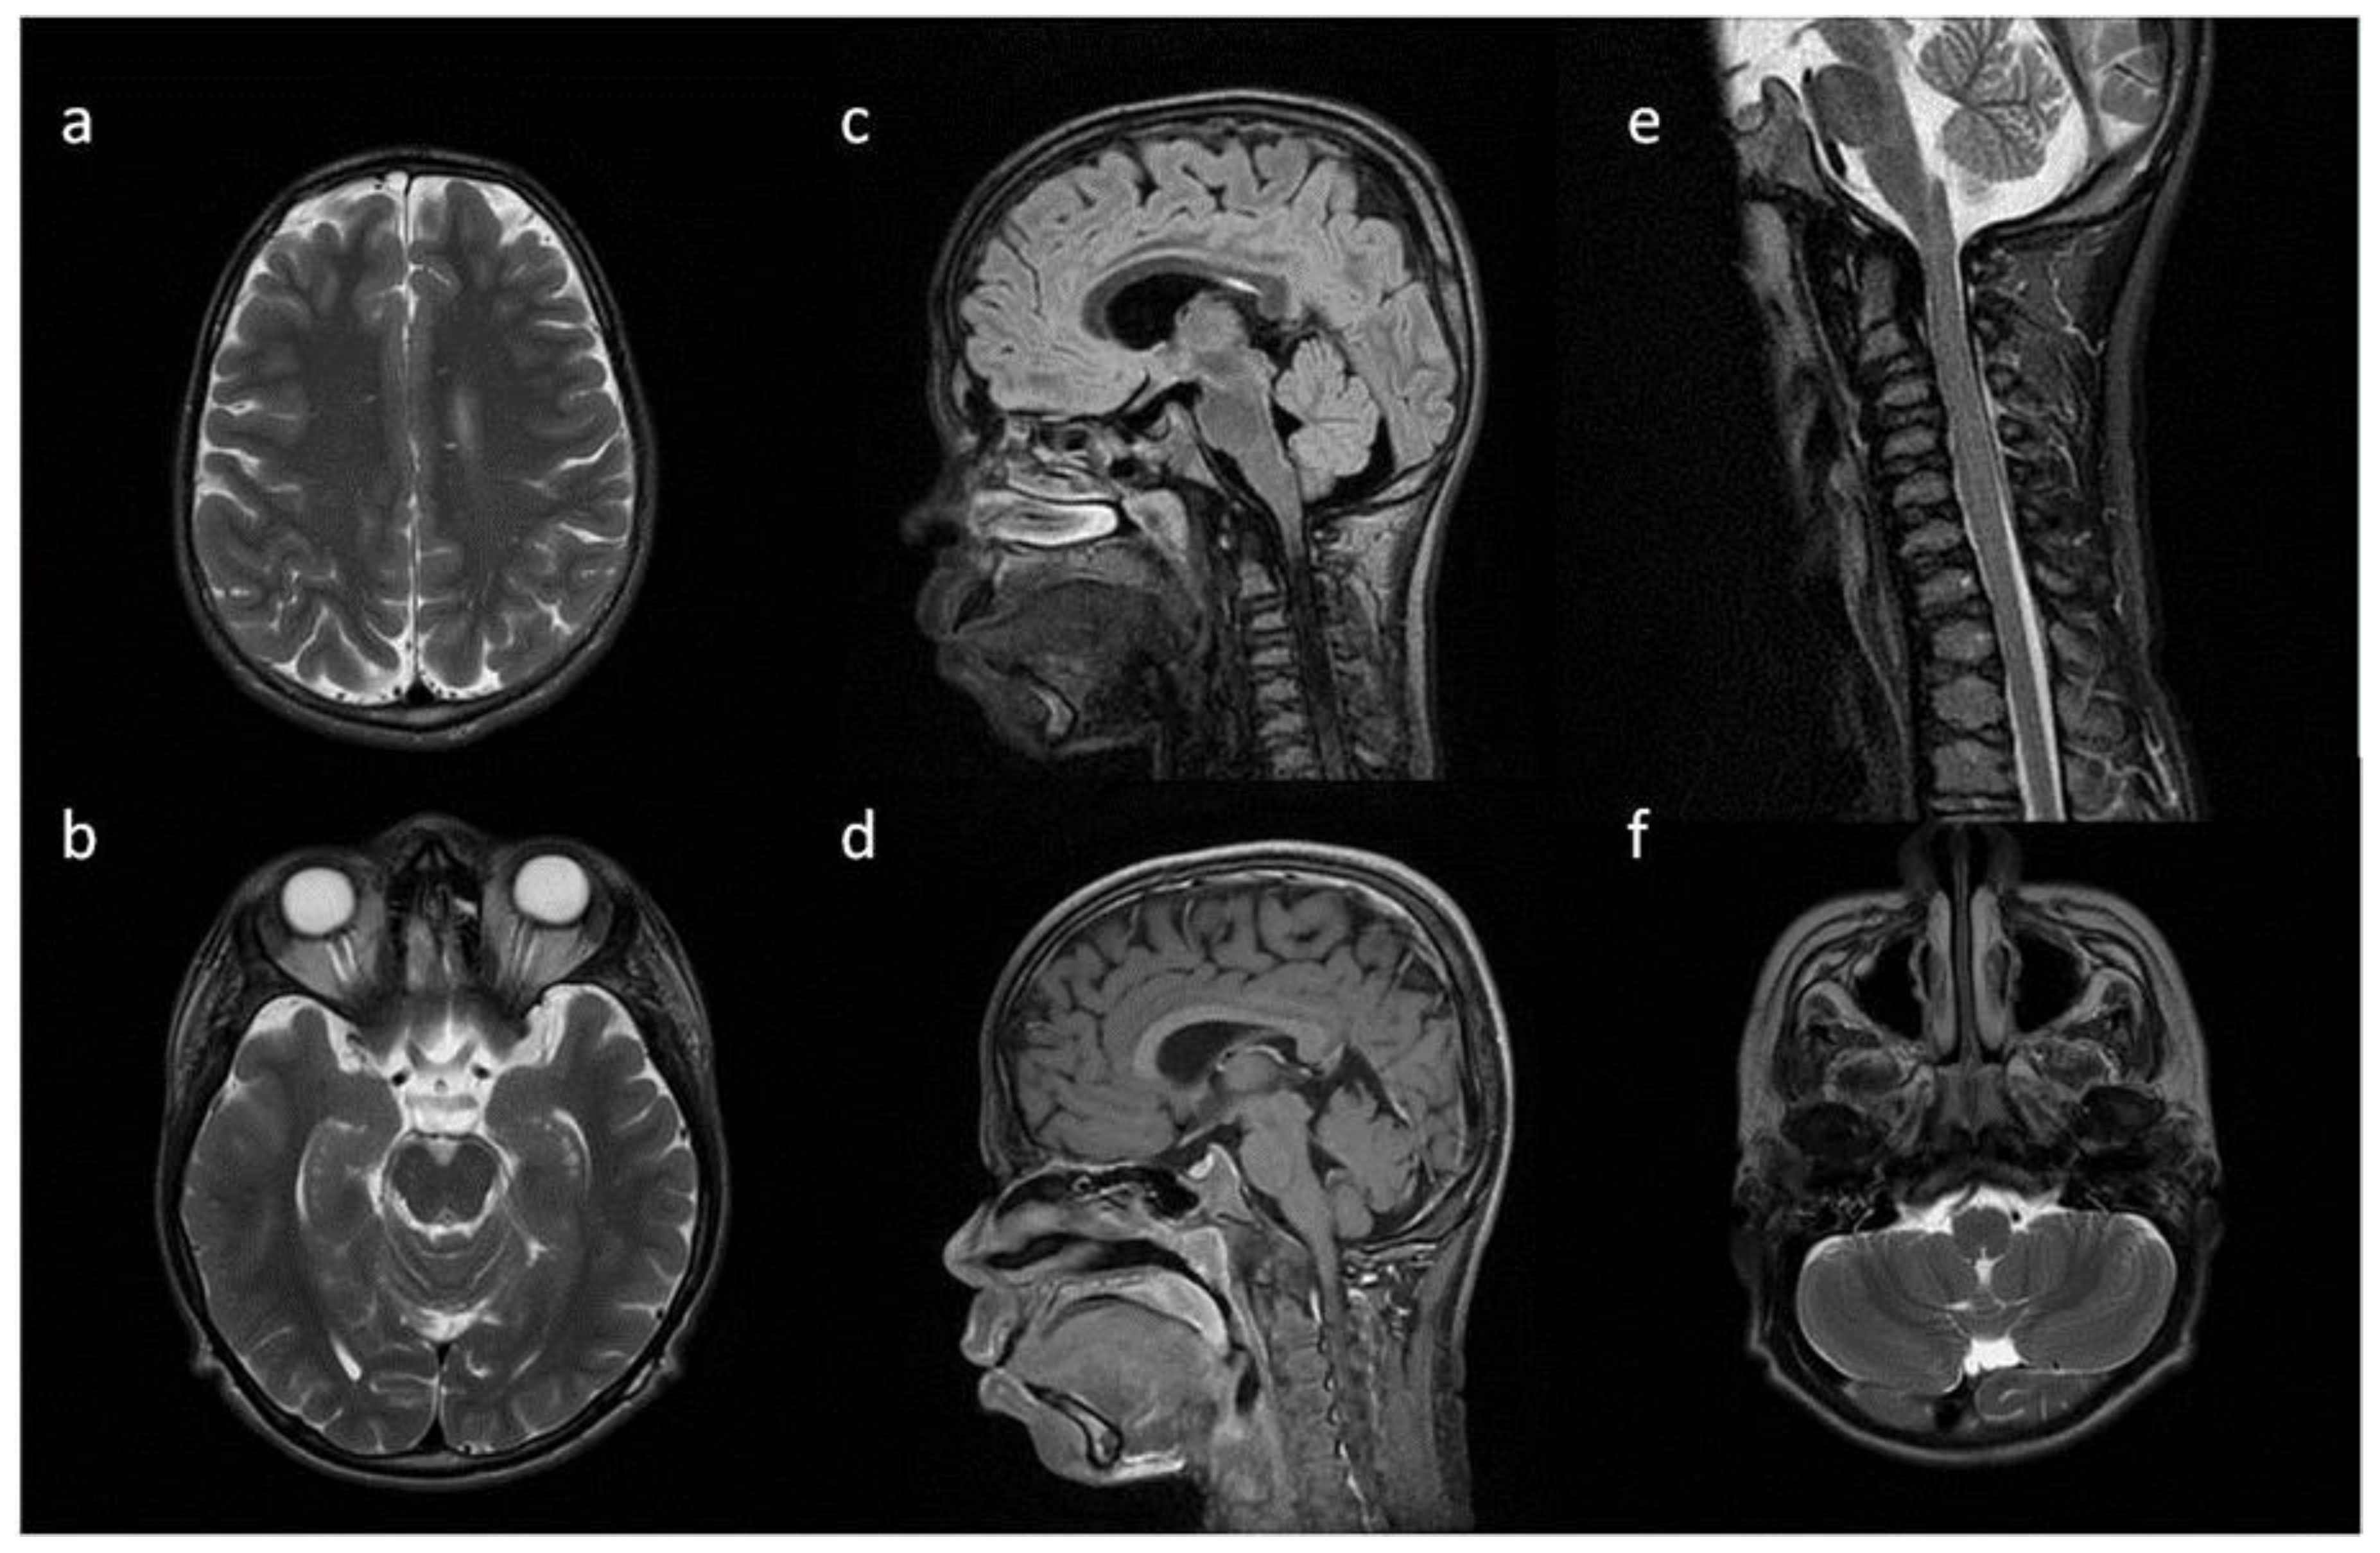

7. Neuroimaging—Methods

8. Brain, Head and Spine—Radiological Symptoms